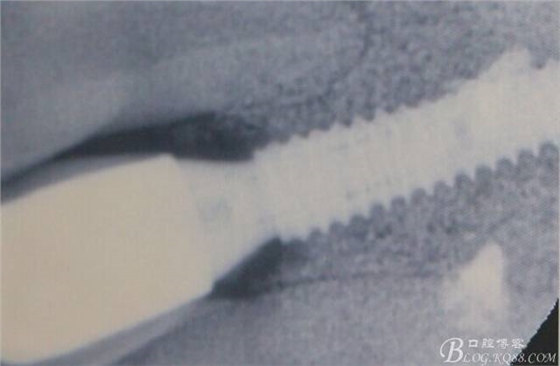

X光顯示沒(méi)有斷根

術(shù)后X光片。

骨高度穩(wěn)定。